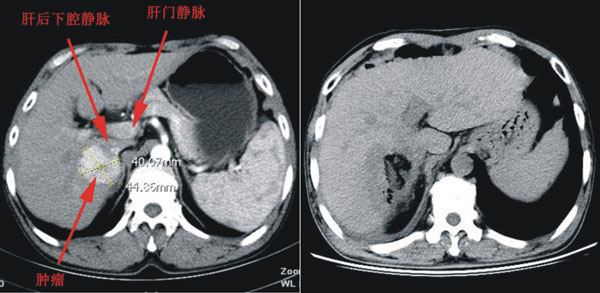

11月21日,由黎一鸣教授、刘清峰副主任医师、陆宏伟副主任医师、李华主治医师对患者实施了肝癌切除术。术中紧贴下腔静脉将肝脏肿瘤游离至第二肝门的下方,在术中B超的引导下,在肝内各个脉管之间的区域,以精准的定位和精细的操作在肝内选择一个安全并尽可能达到根治目的的切面。由于准备充分,整个手术过程有条不紊、配合严密,历时2个半小时,术中出血300ml,完整切除了肿瘤。手术过程未阻断肝门,最大程度的保护了患者的肝功能。术后患者很快清醒拔管,生命体征平稳,目前康复良好,各项检查指标均趋于正常,拟于近日出院。

术后CT影像学对比